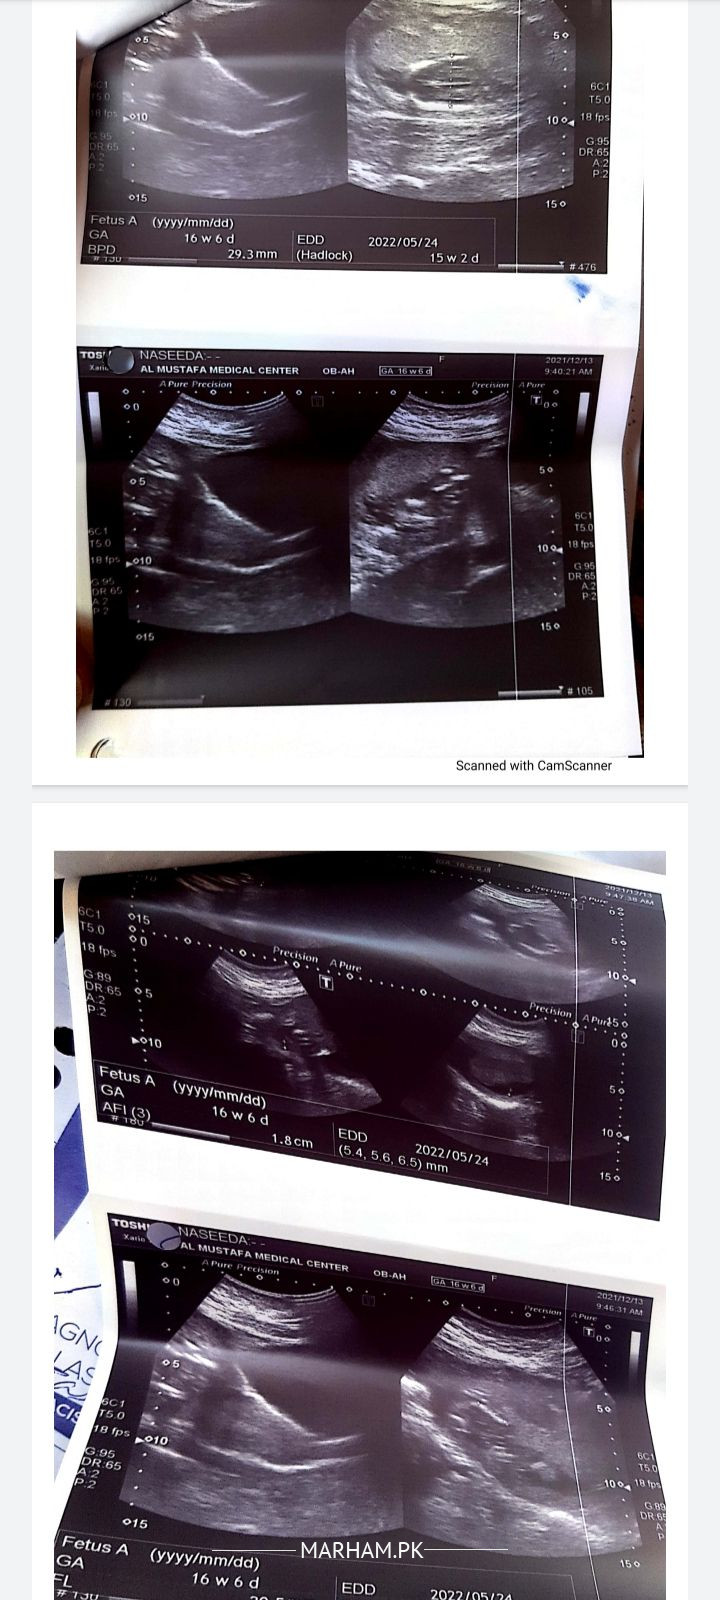

assalamualaikum Dr ya reports kia theek hai baby ke kia condition hai Dr nai oprate ka kaha hai Kai infection horaha hai please Dr guide krai

plz get your ultrasound done by a senior radiologist. its too early to have operation at this stage.

ultrasound me bche ka pani km he .dobara colour doppler kraen